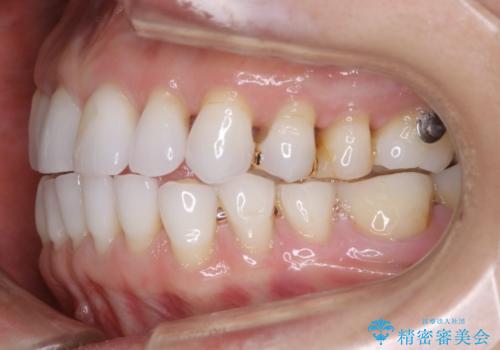

- 歯ぎしりや食いしばり、噛み合わせの治療とガタつきを治したいとのことでご来院されました。

検査の結果、前歯と臼歯の高さに差があり、前歯が全く当たらない状態になっているため歯ぎしりによって奥歯が削れてしまっているという状態でした。

マウスピースの矯正装置を用い、ガタつきを治しつつ奥歯を沈めていくことで噛み合わせ全体の改善を図りました。